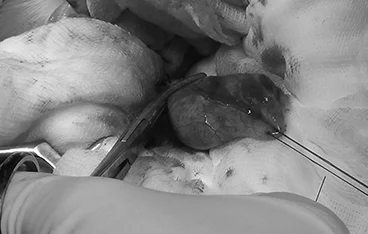

• 횡격막탈장

• 횡격막탈장 수술 전

횡격막탈장 수술 후